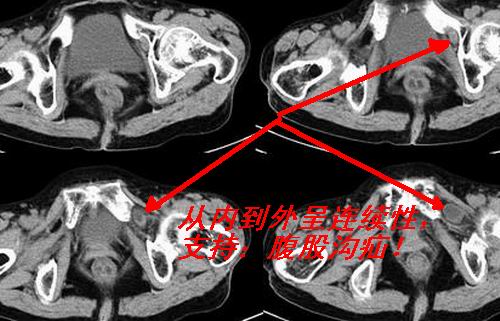

患者女性75岁,腹痛9h余,左腹股沟区可触及一包块,境界不清,压之疼痛明显。

左侧腹股沟股疝。

疝囊经股环,股管向股部卵圆窝突出的疝称为股疝。多见于中年以上妇女。这是因为女性骨盆较宽广,联合肌腱和腔隙韧带较薄弱,以致股管上口宽大松弛的缘故。

腹股沟嵌顿性疝是肯定的,但结果还是没公布是什么疝

左腹股沟嵌顿性疝